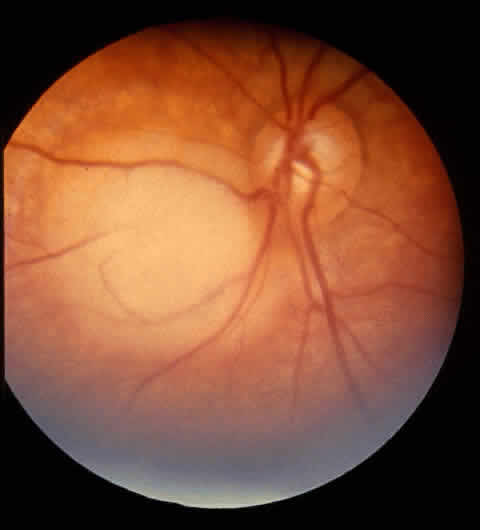

Several tumor growth patterns occur in all retinoblastomas. Endophytic growth (61%) occurs when the tumor grows into the eye relative to the retina. Ophthalmoscopy shows that this tumor sits on the retina (Fig. 2). Exophytic growth (39%) occurs when the tumor grows toward the choroid relative to the retina. Presentation is subretinal.66 Exophytic growth is associated with glaucoma and choroidal invasion. Diffuse infiltration of retinoblastoma represents up to 2% of retinoblastoma cases.67 Retinoma is a benign or spontaneously regressed variant representing less than 2% of all retinoblastomas.68 Malignant transformation has been reported.69 Retinoma may represent a heritable mutation.70

Fig. 2. Localized retinal lesion.